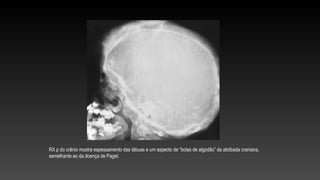

RX p do crânio mostra espessamento das tábuas e um aspecto de “bolas de algodão” da abóbada craniana,

semelhante ao da doença de Paget.